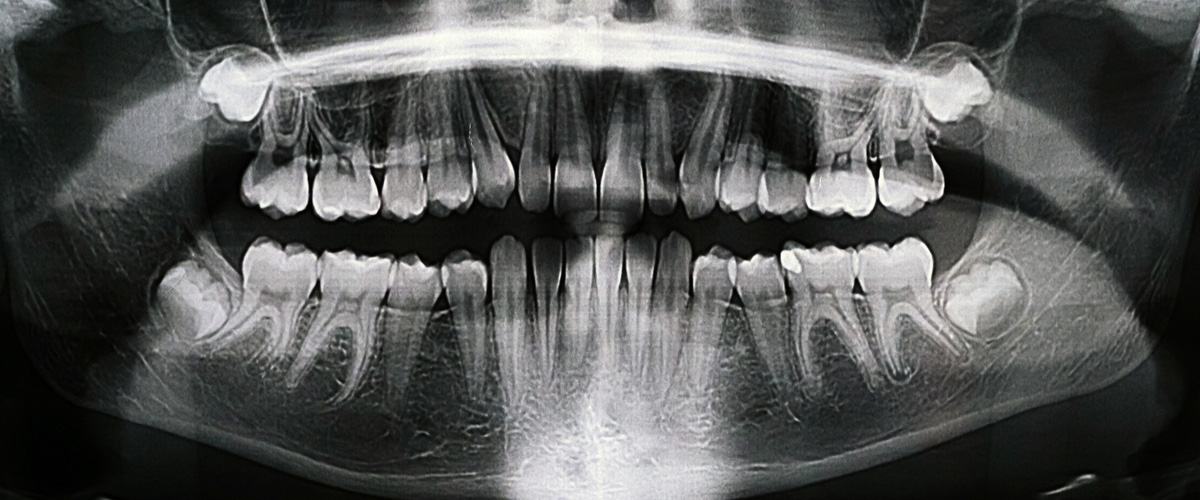

State of the Art Tools, Technologies & Techniques